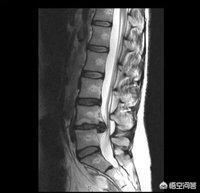

L4-5椎间盘突出症

L4-5椎间盘突出,这个几率相对于前两者要低,因此,我把它放在最后,可是也不能排除是否为L4-5椎间盘突出症造成的,因为麻木的部位恰巧在L5神经的行走路线上,这种问题的处理要进行手法复位,去掉腰部的激痛放射点。